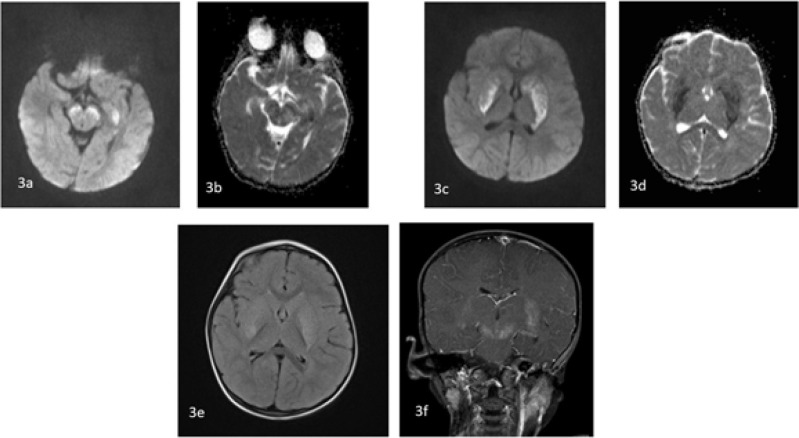

Results: There were 10 cases in the age range of 1-15 years. All the cases had elevated COVID-19 antibodies with history of contact 2-3 weeks prior except one who was positive for COVID-19 infection. Two cases presented with acute ascending paralysis suggestive of Guillain-Barre syndrome. Four cases presented with features of encephalopathy with clinical presentation fulfilling the criteria of Multisystem inflammatory syndrome in children. One case presented with fever and focal seizures with MRI showing sagittal sinus thrombosis, and one presented with fever and altered sensorium with MRI showing leukoencephalopathy. One child had cerebral mucormycosis without any evidence of immunosuppression. There was one child with features of encephalopathy with active COVID-19 infection.